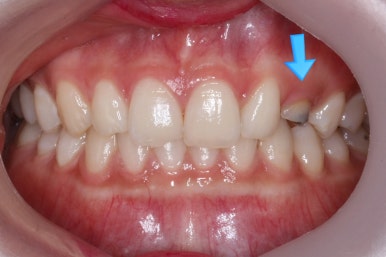

위 사진들은 부산매복치아교정 키다리아저씨치과에 처음 내원하셨을 때의 모습입니다.

화살표 표시한 부분이 바로 영구치 송곳니가 있어야 할 자리인데, 매복이 되어있고 대신 유치가 여전히 남아있는 모습입니다.

환자분의 나이가 만으로 15세였는데, 치과에 처음 올 때 해당 치아가 영구치가 그냥 썩은 줄 알고 오시는 경우가 많습니다.

X-ray를 찍어보고 하면 그 때서야 해당 치아는 유치이며 영구치 송곳니는 뼈 속에 묻혀 있는 것을 알게 되지요.

보통 송곳니는 초등학교 5학년 전후로 나오게 되는데, 이 환자분은 유치가 남아있는 것을 마치 영구치가 나온 것으로 착각하셨던 경우입니다.